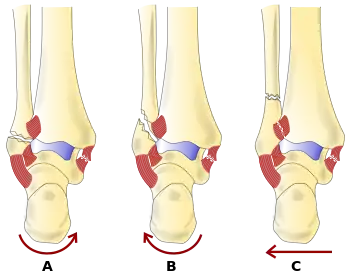

The cause may include excessive stress on the joint such as from rolling an ankle or blunt trauma.[2][1] Types include lateral malleolus, medial malleolus, posterior malleolus, bimalleolar, and trimalleolar fractures.[1] The need for X-rays may be determined by the Ottawa ankle rule.[2]

Anatomy

The ankle region refers to where the leg meets the foot (talocrural region).[6] The ankle joint is a highly constrained, complex hinge joint composed of three bones: the tibia, the fibula, and the talus.[7][8] The weight-bearing aspect of the tibia closest to the foot (known as the plafond) connects with the talus. This articulation (where two bones meet) is primarily responsible for plantarflexion (moving your foot down) and dorsiflexion (moving your foot up).[8] Together the tibia and fibula form a bracket-shaped socket known as the mortise, into which the dome-shaped talus fits.[9] The talus and the fibula are connected by a strong group of ligaments, which provide support for the lateral aspect of the ankle. These ligaments include the anterior talofibular ligament (ATFL) and the posterior talofibular ligament (PTFL).[10] The calcaneofibular ligament (CFL), which connects the fibula to the calcaneus, or heel bone, also provides lateral support. The deltoid ligament provides support to the medial part of the ankle (closest to the midline). It prevents the foot from excessively everting, or turning outwards while also preventing the talus from externally rotating.[10] The distal parts of the tibia and fibula are connected by a connective tissue network referred to as the syndesmosis, which consists of four ligaments and the interosseous membrane.[10]